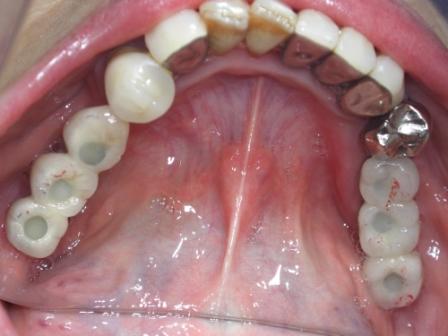

でオペを開始しました。ケースとしては上顎の無歯顎で2本インプラントを入れマグネットで仕上げます。

午後はインプラントのかぶせものです。長年なかった奥歯での食事がようやくできますね